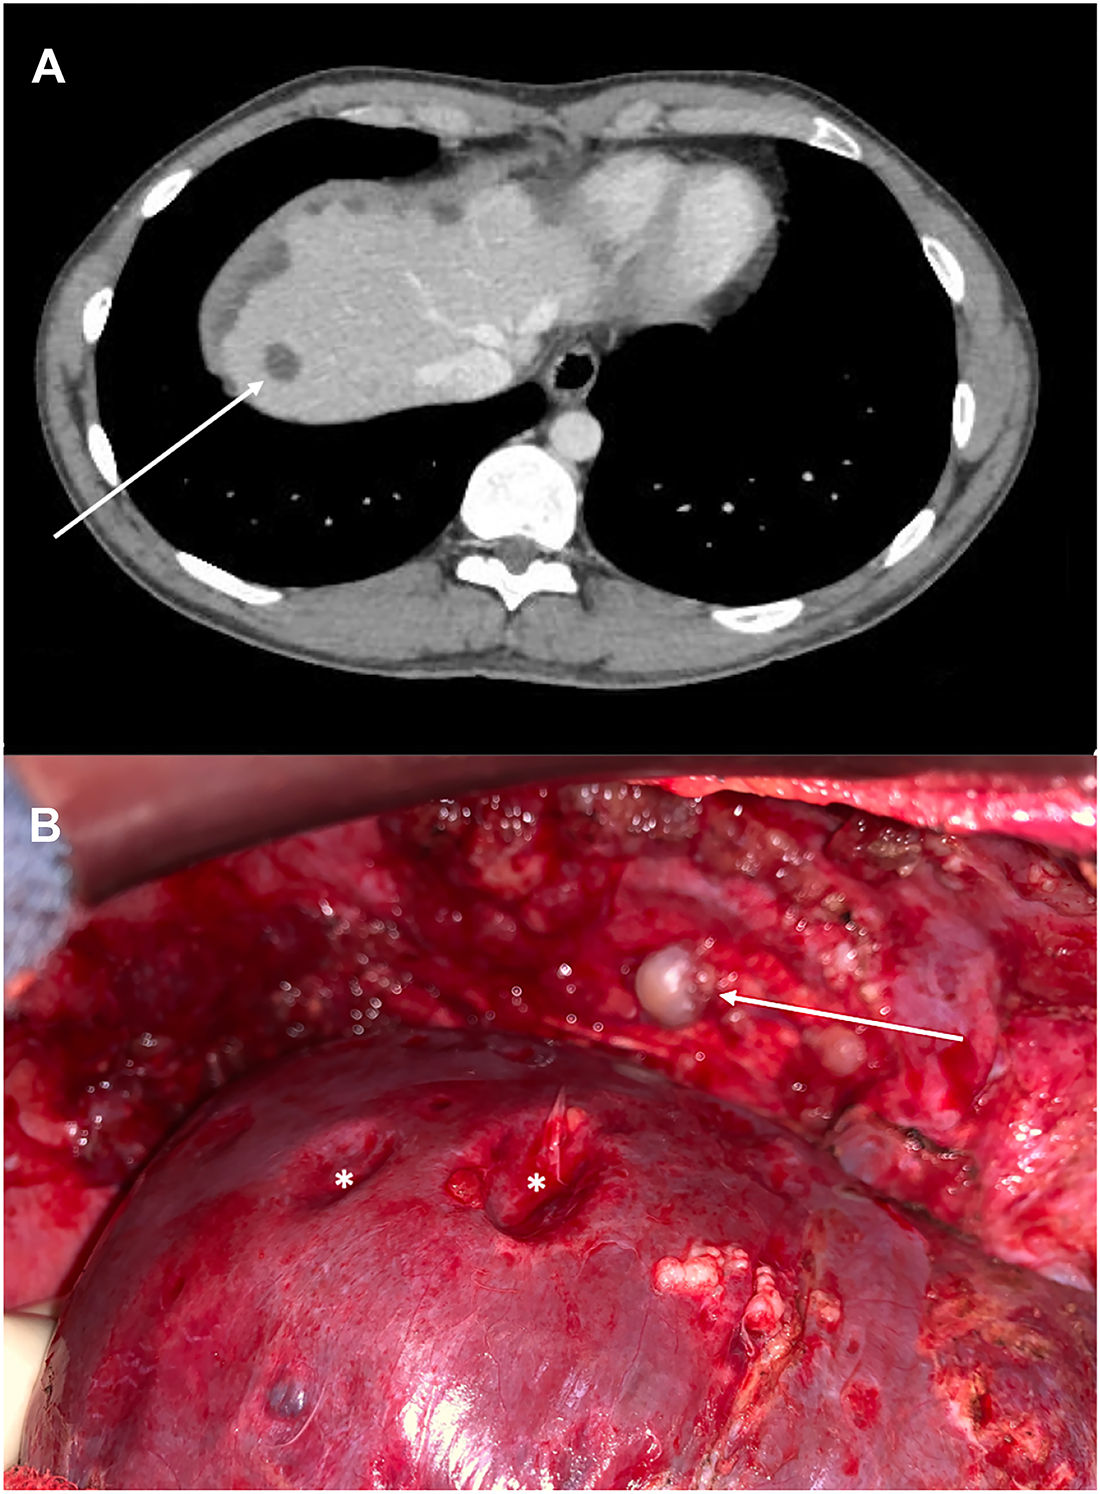

A 27-year-old male presented with abdominal pain and asthenia. Abdominal CT-scan identified left colon mass associated with synchronous peritoneal metastases (PM) and hypodense liver suspicious lesions (Figure 1A, arrow). Colonoscopy with pathological analysis of colic biopsies confirmed an adenocarcinoma with microsatellite instability, allowing to perform neoadjuvant immunotherapy (Pembrolizumab). Explorative laparotomy confirmed the PM with the presence of implants on the right diaphragmatic dome (Figure 1B, arrow) exerting extrinsic compression of the liver (Figure 1B, star). A complete cytoreductive surgery combined with Mitomycin C based-hyperthermic intraperitoneal chemotherapy (HIPEC) was performed.

CT-scan (A) revealed hypodense liver lesions (arrow) at the diagnosis of left colon adenocarcinoma with synchronous peritoneal metastases. Explorative laparotomy (B) highlighted diaphragmatic peritoneal metastases (arrow) exerting pressure on the liver surface, called «scalloping» (star).

PM are often located in Douglas pouch, parieto-colic gutters, and also in the subphrenic space. Therefore, peritoneal tumor implants under the diaphragm can mimic liver metastases on CT-scan [1, 2] by exerting pressure on the liver surface, called “scalloping” [3]. It is essential to distinguish diaphragmatic PM and liver metastases and to carry out further investigations in case of doubt, because of their different therapeutic strategies.